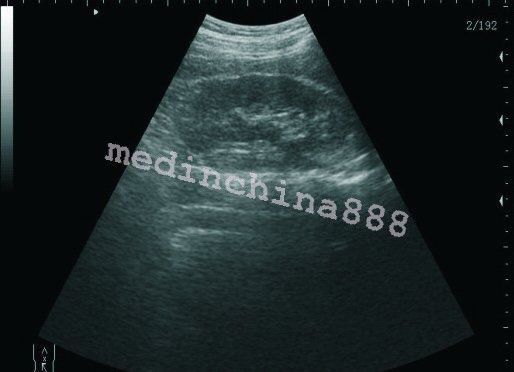

The Laptop LCD Digital 10.1-Inch Ultrasound Scanner is designed for high-quality imaging. This portable device offers detailed visuals, allowing healthcare professionals to deliver accurate diagnoses effortlessly. Equipped with both convex and transvaginal probes, it enhances versatility in various medical procedures. Its compact design ensures that you can carry it easily between locations, making it an essential tool for any medical practice. The user-friendly interface further simplifies operation, so you can focus on patient care without unnecessary distractions.

This ultrasound scanner is not only portable but also built for convenience. The 10.1-inch LCD screen displays clear images, which means you can view results in real-time without any lag. It provides essential features like freeze and rewind functions, enabling you to review images quickly. Additionally, because it connects easily to printers or USB devices, you can generate hard copies of your findings without any hassle. So, whether in a clinic or at a patient's home, this laptop ultrasound scanner adapts to your needs.